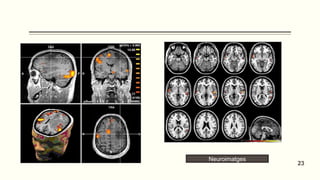

Neuroimatges

23